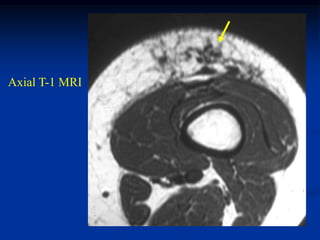

Case #1213

46 year male with

lymphangioma arm

Axial PD MRI

Another T-2 MRI